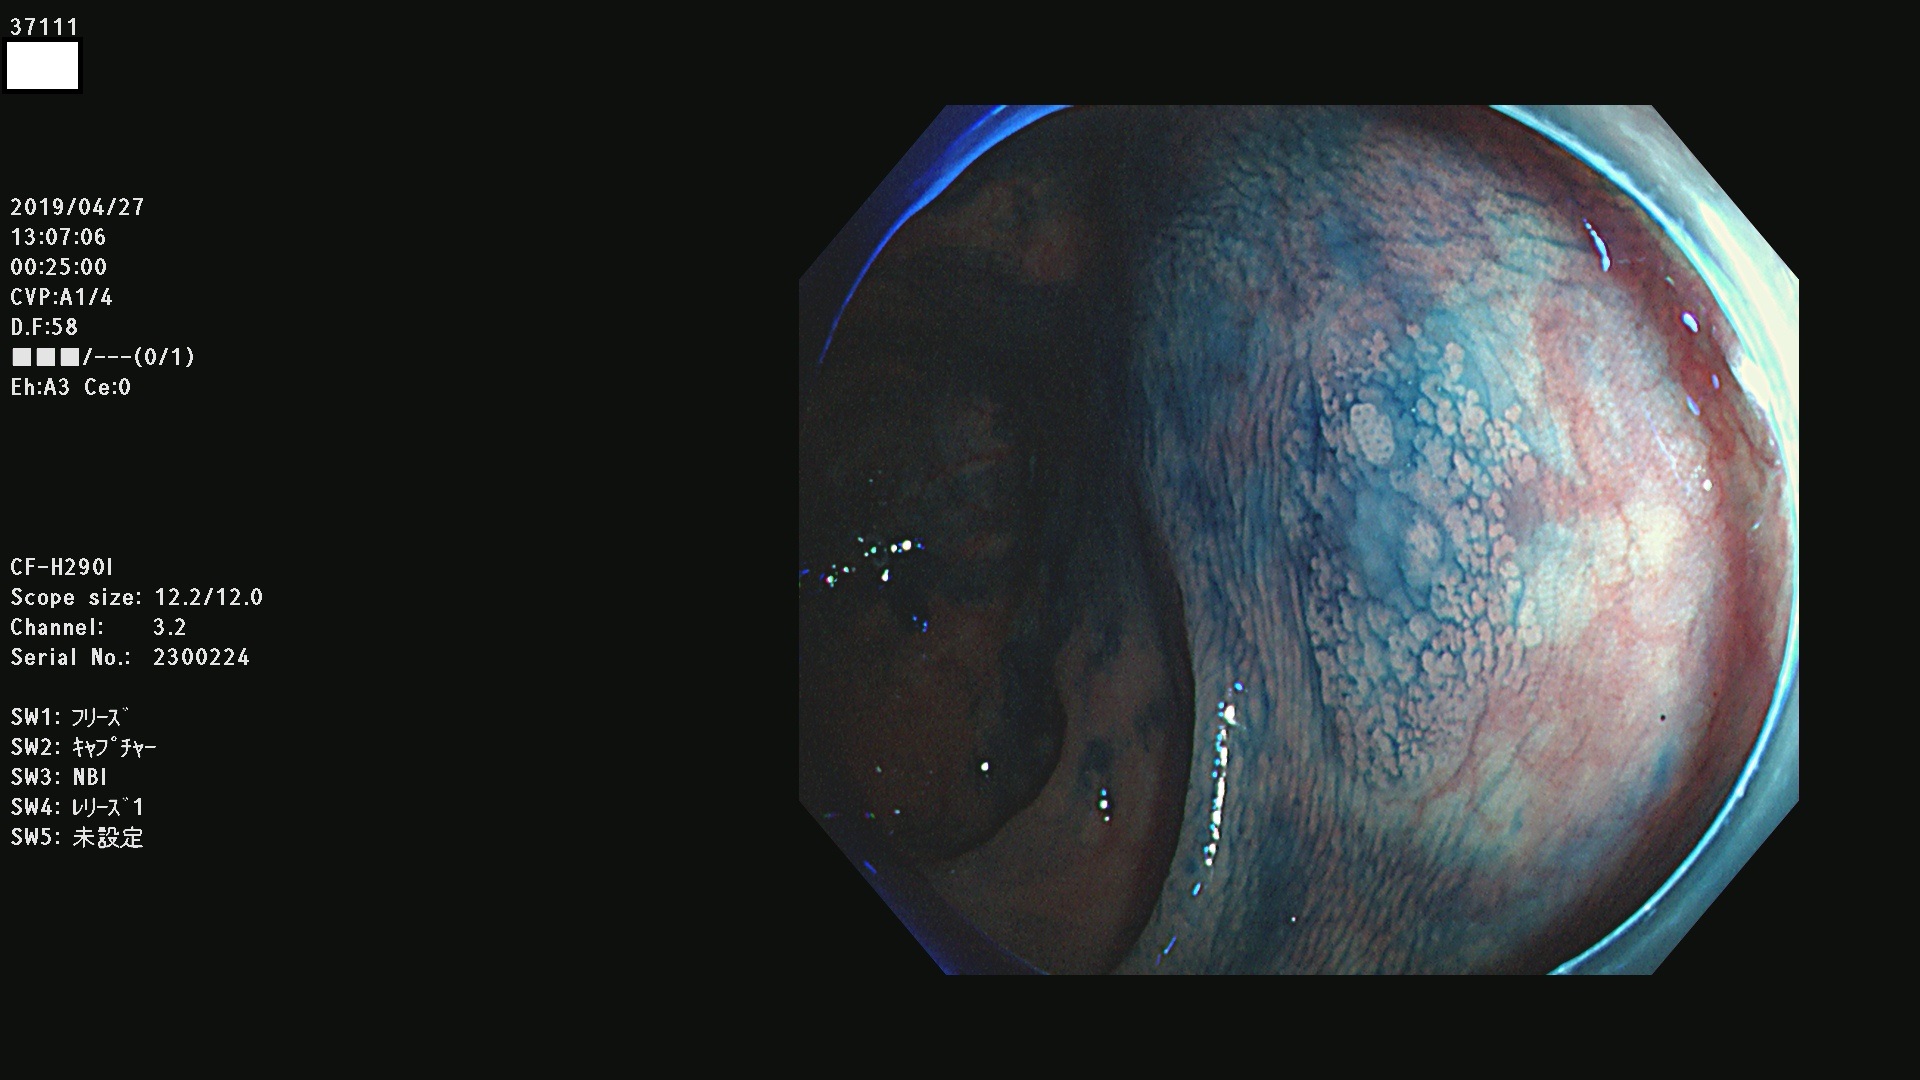

37100 37101 37102 37104 37106 37108 37110 37111 37112 37113 37115 37118(SSAPのみ) 37120 37122 37123 37124 37127(SSAPのみ) 37128(SSAPのみ) 37131 37132 37133 37134 37135 37139 37141 37142 37143 37144(SSAPのみ) 37145 37147(SSAPのみ) 37148 37149 37150 37153 37154 37157 37159 37161 37162 37163 37164 37165 37166 37167 37168 37169 37170 37171 37172 37173 37175(SSAPのみ) 37176 37177 37178 37180(SSAPのみ) 37181 37184 37185 37186 37187 37188 37189 37190 37192 37194 37197 37198

発見困難で危険性の高い平坦型病変(上記100名より抽出)